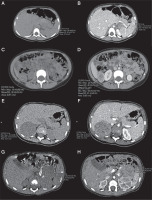

Figure 1

Axial unenhanced abdomen computed tomography (CT) scans (1A, 1C, 2A, 3A) and enhanced CT scans (1B, 1D, 2B, 3B) demonstrate adrenal tumours in our cases (min, max, and mean depict the respective values for the lowest, highest, and mean Hounsfield units (HU), as derived from the software for the region of interest marked by the investigator). A) Case 2, axial unenhanced CT scan demonstrates tumour act in the left adrenal gland, dimensions: 50 × 40 × 30 mm, mean 42 HU. B) Case 2, enhanced CT scan demonstrates tumour in the left adrenal gland, dimensions: 50 × 40 × 30 mm, mean 79 HU. C) Case 2 –axial unenhanced CT scan demonstrates metastases in the right adrenal gland, dimensions: 27 × 29 × 36 mm, mean 35 HU. D) Case 2, axial enhanced CT scan demonstrates metastases in the right adrenal gland, dimensions: 27 × 29 × 36 mm, mean 81 HU. E) Case 3, axial unenhanced CT scan shows an inhomogeneous tumour in the right adrenal gland, dimensions: 53 × 43 × 59 mm, ∅ 50 mm, mean 31 HU. F) Case 3, axial enhanced CT scan shows an inhomogeneous tumour in the right adrenal gland, dimensions: 53 × 43 × 59 mm, ∅ 50 mm, mean 83 HU. G) Case 4, axial unenhanced CT scan shows an inhomogeneous tumour, with peripheral calcifications in the left adrenal gland, dimensions: 49 × 39 × 45 mm, ∅ 45 mm, mean 33 HU. H) Case 4, axial enhanced CT scan shows an inhomogeneous tumour with peripheral calcifications in the left adrenal gland, dimensions: 49 × 39 × 45 mm, ∅ 45 mm, mean 94 HU

The first symptoms in the study group were hyperandrogenic signs in the form of the appearance of pubic hair and clitoromegaly. No manifestations of cortisol excess were observed. The median age at the time of diagnosis was 1.5 years. The median time between the first symptoms and diagnosis establishment was 1.5 months (min: 0.25, max: 5 months). The median tumour diameter in CT examination was 50 mm (min: 49.6 mm, max: 70 mm) (Figure 1).